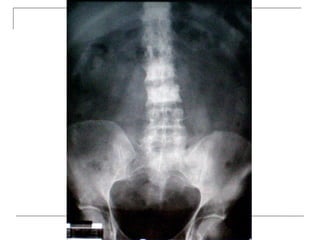

Plain radiograph

 AP

-loss of lumbar lordosis

-reduced disc space

-osteophytes

-deformity

-fracture (increase interpedicular distance)

-osteoporosis

-pedicle disruption

 Lateral

-fracture/wedging

-kyphosis

-spondylolisthesis

 Oblique

-spondylolysis (SCOTTIE DOG)

Plain x-rays